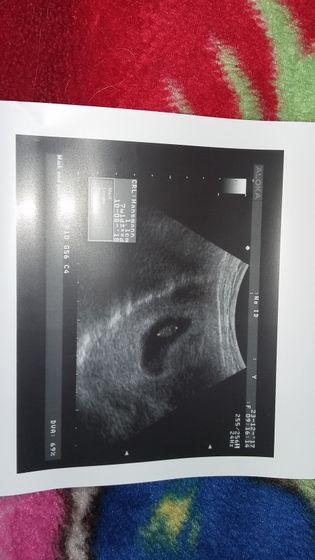

Мои надежды и молитвы все таки сбылись. У второго малыша забилось сердечко??? мои крошечки как же я рада что вы оба живы и здоровы. На данном этапе все хорошо. Один малыш соответствует 7 нед второй 8. Сердечко у одного 163/165 у второго. Конечно узистка мне сказала что это очень сложная беременность. И что гарантий мне никто не даст что все будет хорошо с детками. Но я верю в лучшее. Фото крошек? нафоткала их из разных углов? двоих не смогла поймать

Здорово???хорошо что все хорошо??? а мы 11 и 13 мм?